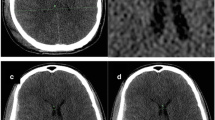

Illustrative example of trajectory planning. In-app view on an Apple iPad of a patient with narrow ventricles and traumatic brain injury (TBI). A Initially, an anterior coronal image is imported and adjusted in size to the image overlay. B The entry point and the guiding tool’s base are virtually placed on the scalp surface. C Then, the angulation is adjusted to place the tube’s direction towards the foramen of Monro in the ipsilateral ventricle (red dashed line), and the catheter length (dot on red dashed line) and distance to midline (dot on green dashed line) are measured, accordingly. Finally, all relevant calculations are presented

Application of the ventricular catheter guide (Thomale Guide, Christoph Miethke, Potsdam, Germany) was previously described for controlled implantation of ventricular shunt catheters [25, 26]. Most importantly, the catheter guide enables insertion of the ventricular catheter orthogonally to the sagittal plane with an individual, adjustable angle in coronal orientation in relation to calvarial slope [21]. The catheter trajectory is calculated in advance of EVD implantation by means of a mobile health app (iOS, iTunes: Thomale Guide App, Christoph Miethke, Potsdam, Germany) on a smartphone (iPhone, Apple, Cupertino, USA) or tablet computer (iPad, Apple, Cupertino, USA) (Fig. 1). As the ventricular catheter is placed bedside and percutaneously through a straight incision, in contrast to the standard application of the Thomale Guide placed on the skull via a skin flap, the entry point must be planned on the surface of the scalp instead of the skull bone. In summary, the application starts with taking a picture of a cranial CT or magnetic resonance imaging (MRI) from a DICOM viewing software or importing imaging material from a photo gallery. The image should be a coronal orientation with the lateral ventricles shown at the level of the anterior commissure. In moderate size ventricles, the coronal section should be in strict vertical orientation along the spine axis, while in narrow ventricles, the coronal plane should be individually tilted slightly anterior, optimally along the trajectory of the catheter placement. The image can be taken from a 3D MRI (e.g., MP-RAGE, 3D FFE, VIBE) or CT volume data set reconstructed by regular DICOM viewing software (e.g., Horos, Horos Project, New York, USA; Elements DICOM Viewer, Brainlab, Munich, Germany; RadiAnt DICOM Viewer, Medixant, Poznań, Poland; or MERLIN, Phönix-PACS, Freiburg, Germany) in order to visualize the coronal skin surface as close as possible to the entry site and foramen of Monro. The entry point in the sagittal plane from the nasion can now either be chosen as standard at 11.5 + / − 5 mm by default or measured exactly on the sagittal CT or MRI. The image is adjusted in size to an overlay and calibrated to the bitemporal diameter. This diameter should be determined with the DICOM viewing software in advance. Alternatively, 139 mm is an appropriate established approximation [12]. The next step is to define a paramedian entry point on the scalp surface by finger tapping on the screen with the help of an in-app implemented magnifying glass. Then, the two feet of the guiding tool’s base are virtually placed on the scalp surface bilateral to the entry point at the predefined radius of the guiding tool. The guide will then be presented as a schematic drawing. The preset orthogonal trajectory orientation of the tube is shown. A sliding bar allows the guide’s tube to virtually rotate around the entry point to shift the trajectory towards the ipsilateral ventricle. In addition, the finger is placed on the target within the ipsilateral ventricle to calculate the catheter length. Similarly, the finger is placed on the midline convexity of the skin, to calculate the entry point’s distance from midline.